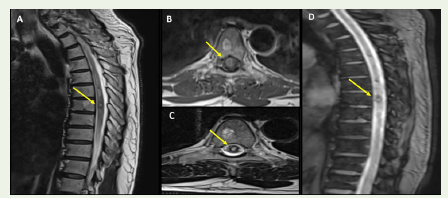

around D7-D8 vertebral levels . MRI of the dorsolumbar spine showed

a cavernous malformation at D7 vertebral level with surrounding

haemorrhage and oedema extending about 13cms longitudinally

[Figure 1A-D].

Figure 1: T2-weighted sagittal (A) and axial (B,C) sections of MRI-spine

showing a hyperintense lesion with a surrounding hypointense rim at

D7 vertebral level, suggestive of cavernoma at D7 vertebral level with

surrounding hyperintensity indicating haemorrhage and oedema extending

longitudinally for about 13cms. The lesion also demonstrated blooming on

GRE sequence (D).